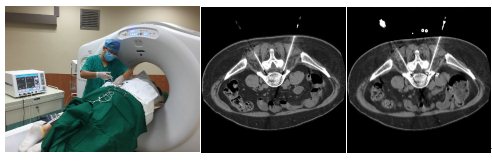

8月20日,在完善术前检查和准备后,马永强医师在CT引导下成功对患者实施了选择性神经根阻滞联合脉冲射频微创介入治疗手术,手术不需开刀和住院,在CT扫描定位“责任神经根”后,只需对穿刺点进行局部麻醉,在CT引导下将两根20G细针精准插入到神经根旁,进行神经根阻滞和脉冲射频治疗。

目前,患者疼痛视觉模拟评分(visual analog scale VAS)由术前8分减轻至1分,疼痛已经基本消失。真正体现了微创、快速、准确的救治理念。